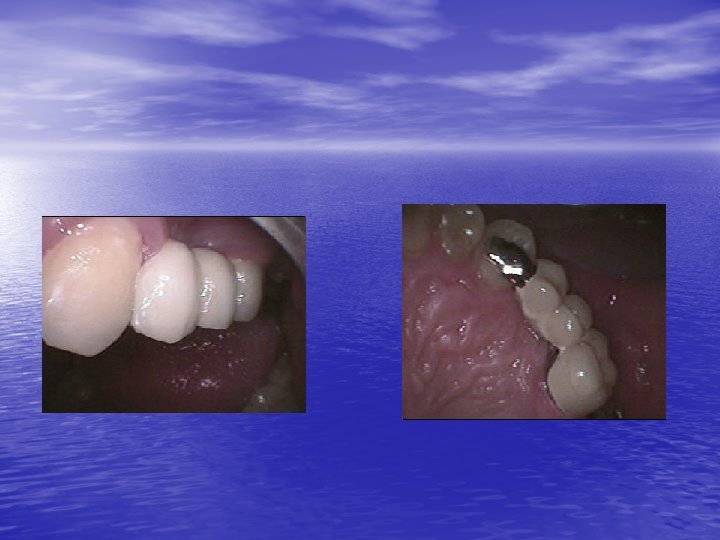

First clinical case